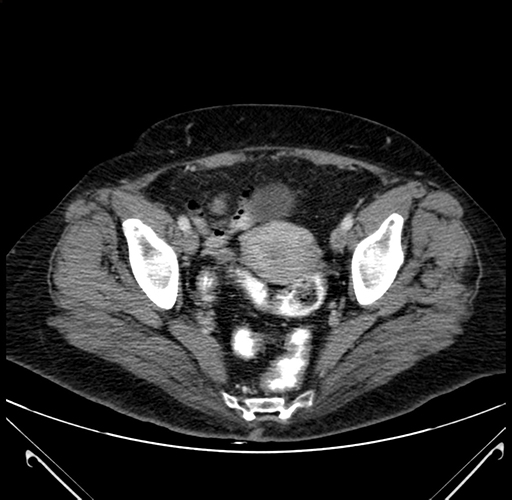

Axial Venous

Imaging analysis

Based on your CT findings, which issue(s) would give reason for "planned slowing down moment(s)" in this case?

Considering a standard right hepatectomy procedure, what step(s) of the operation would you do differently in this case?